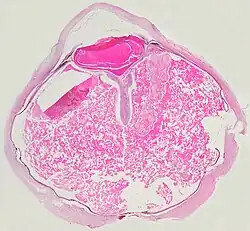

- Pathologische Präparate beim Morbus Coats

-

V-förmige Ablösung der Netzhaut durch das Exsudat. -

Eine ausgeprägte Netzhautablösung und ein gelbliches Exsudat unter der Netzhaut, das Cholesterinkristalle enthält, sind charakteristisch für den pathologischen Befund.

Unter dem Mikroskop kann die Wand der Netzhautgefäße in manchen Fällen verdickt, in anderen ausgedünnt erscheinen. Hinzu kommt eine unregelmäßige Erweiterung der betroffenen Gefäße.[25] Charakteristisch ist ein Exsudat, das sowohl aus Cholesterinkristallen, mit Cholesterin und Pigmenten beladenen Makrophagen, als auch aus roten Blutkörperchen und Hämosiderin besteht.[26] An der Netzhaut können sich eine durch das Exsudat ausgelöste granulomatöse Reaktion und in manchen Fällen auch eine durch die Verletzung ausgelöste Gliose finden.[27]